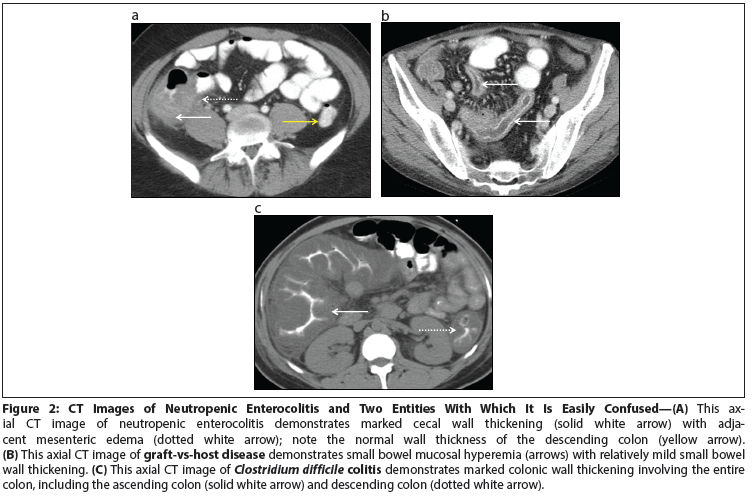

Figure 2: CT Images of Neutropenic Enterocolitis and Two Entities With Which It Is Easily Confused

CT is the imaging study of choice to differentiate neutropenic enterocolitis from other possible causes of pain in a neutropenic patient presenting with fever and abdominal pain. Kirkpatrick et al retrospectively reviewed 76 patients who presented with neutropenia, fever, and abdominal pain. Based on the characteristics of the bowel thickness and mesenteric characteristics, they were able to formulate CT diagnostic criteria that could differentiate between neutropenic enterocolitis, graft-vs-host disease, and C difficile colitis. On imaging, neutropenic enterocolitis has thickened bowel-on average 7 mm thick (range, 4–15 mm) and is associated with mesenteric stranding (Figure 2A). Graft-vs-host disease has minimal bowel wall thickening but significant mucosal enhancement (Figure 2B). C difficile colitis has prominent bowel wall thickening (> 12 mm) and wall nodularity (Figure 2C). By using the combination of the clinical features and CT bowel thickening of > 4 mm, the diagnosis of neutropenic enterocolitis can be more objective, reproducible, and measurable.[23]